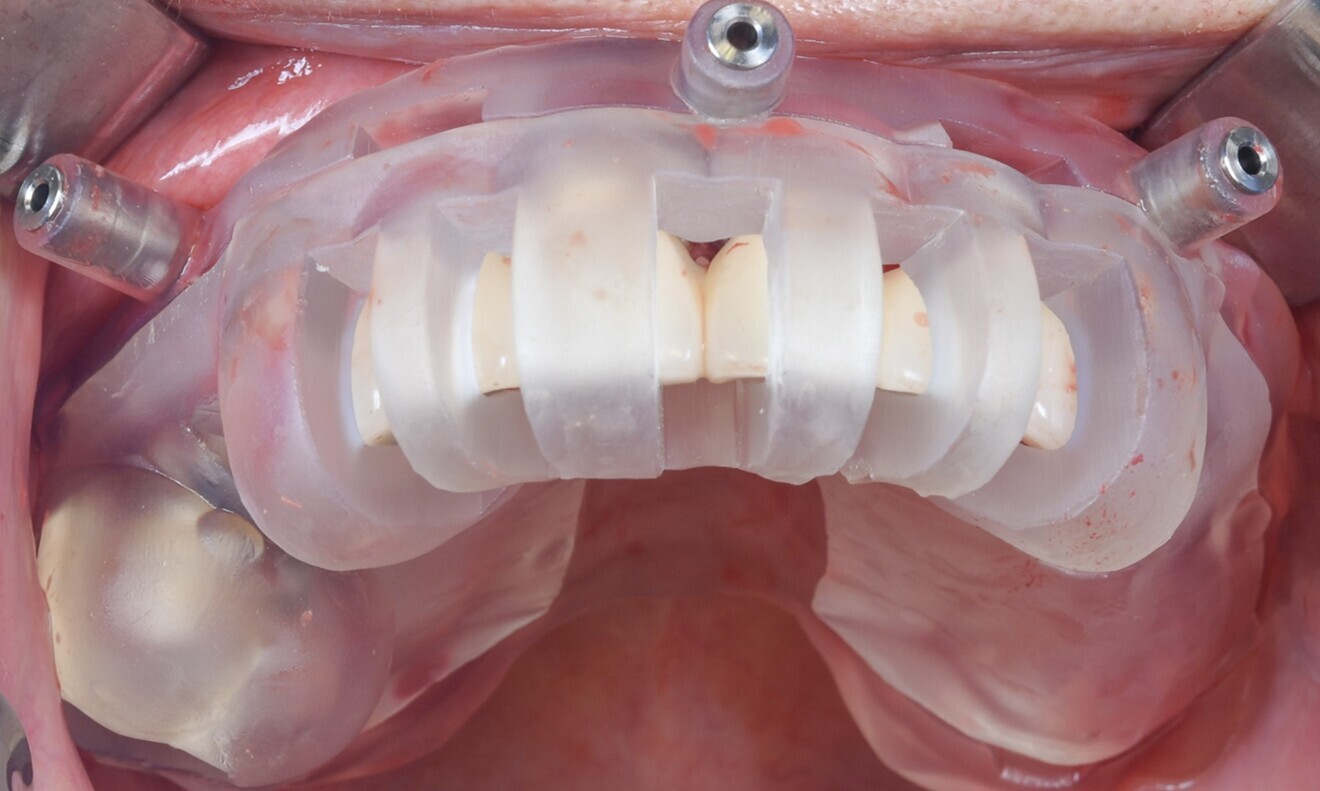

Six Straumann BLT implants made from the material Roxolid and with the SLActive surface (implant #16: 4.8 × 10.0 mm; implant #14: 4.1 × 14.0 mm; implant #12: 3.3 × 14.0 mm; implant #21: 4.1 × 12.0 mm; implant #23: 3.3 × 12.0 mm; implant #26: 4.1 × 14.0 mm) were placed (Fig. 8). The gaps were filled with Straumann XenoGraft, and six temporary titanium copings for screw-retained abutments were subsequently placed (Fig. 9).

Maxillary full-arch impressions were taken, employing appropriate impression copings for an open-tray approach using a polyether impression material (Impregum, 3M ESPE). After a few hours, a dental dam was placed around the temporary copings to protect the fresh surgical sites. The previously prepared temporary prosthesis produced from a resin-based provisional material was then affixed in place (Figs. 10–12).